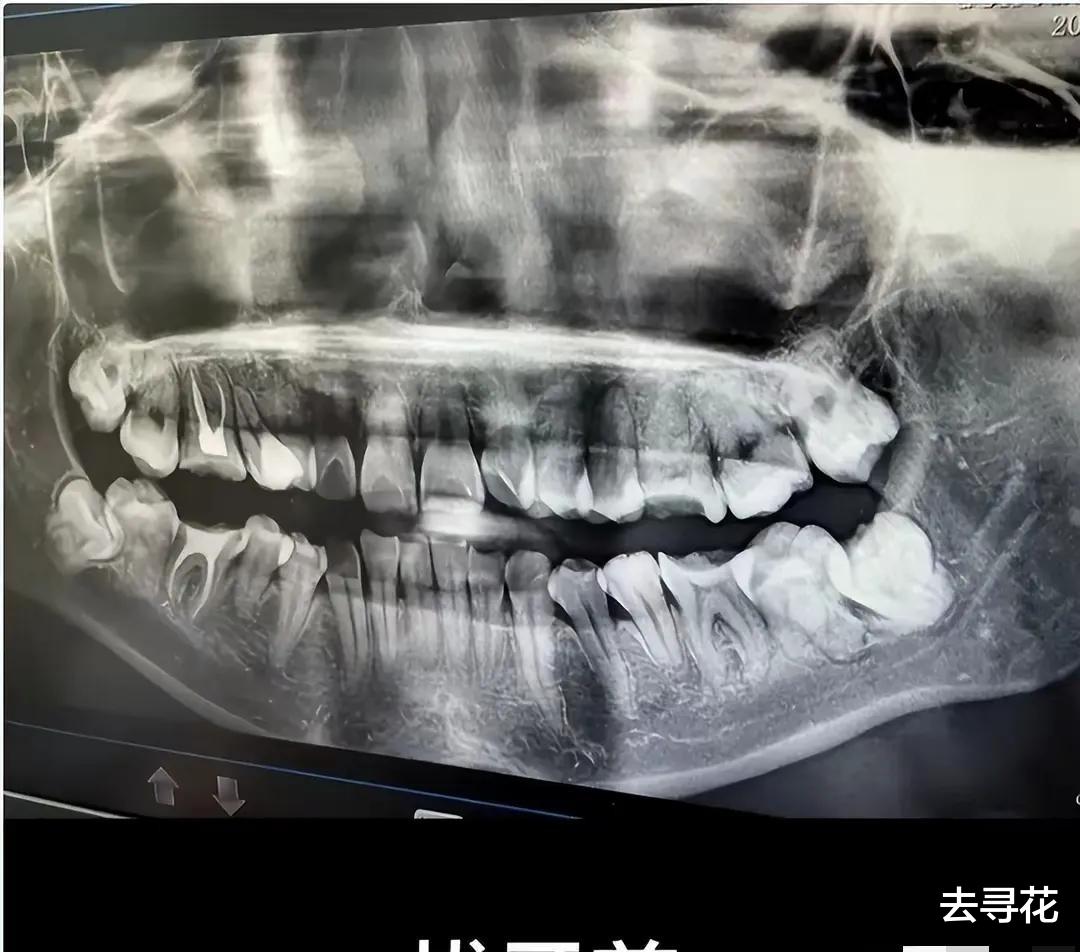

谁会想到,一次普通的拔牙,竟会酿成如此惨剧?吴芳芳的遭遇,让我们不得不深思:究竟是什么样的无力感,压垮了这位母亲?是医生的失误?还是医院冷漠的态度?抑或是,整个社会都欠缺的那份关怀和保护?这颗错拔的牙,不仅带走了吴芳芳的生命,更带走了一个家庭的希望,这又该由谁来承担?

事件中,医院的处理方式,无疑是引发众怒的导火索。拔错牙本身就是医疗事故,而之后医院的敷衍、甚至可能存在的篡改病历,更是雪上加霜,将一个本就绝望的母亲推向了深渊。试想一下,在身心俱疲、遭受巨大委屈的情况下,一个弱势的患者,面对医院的强势和冷漠,是多么的无助和无力?我们常常说,医院是救死扶伤的地方,是守护健康的地方,可当它变得冰冷、冷漠,甚至充满欺瞒之时,又该如何让人相信它?